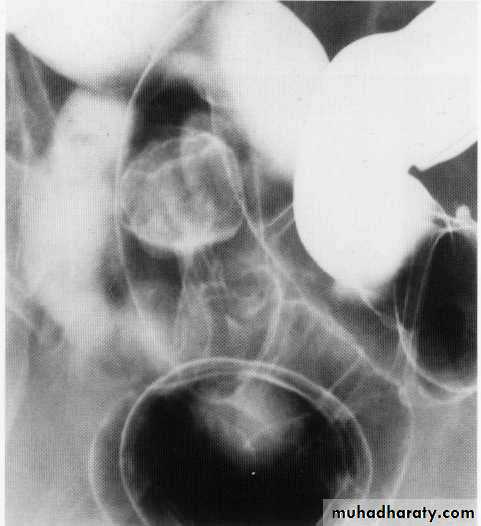

Abnormal haustra toxic megacolon